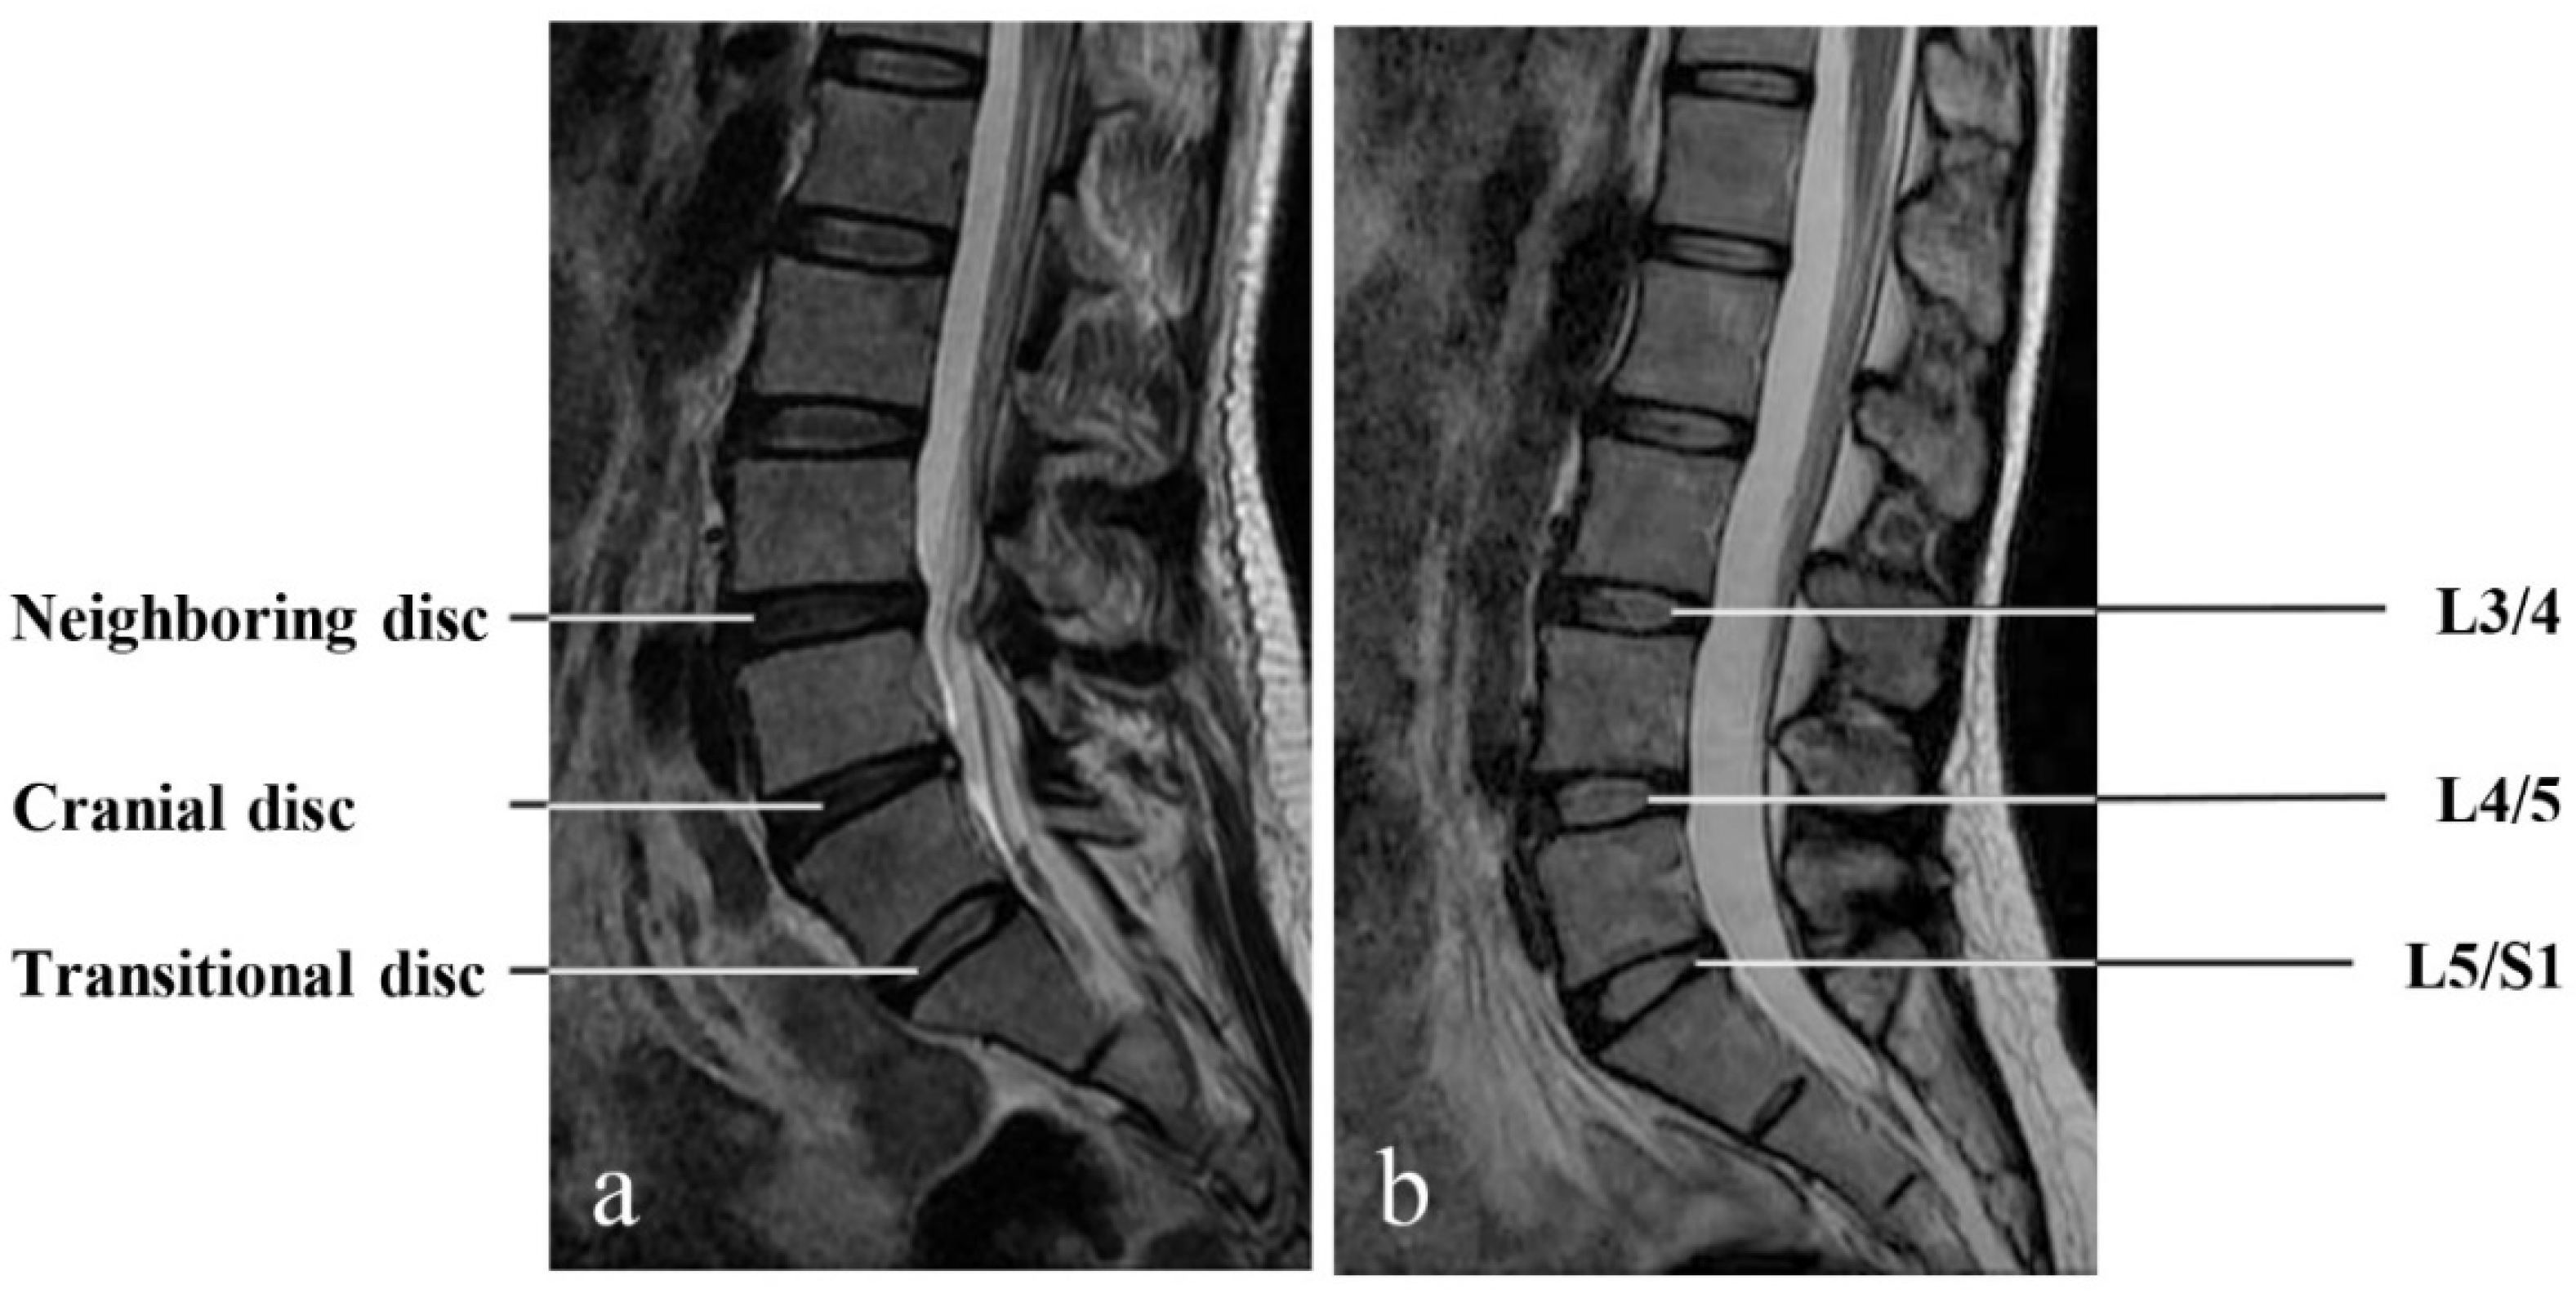

- The Transitional Disc

- The cranial disc

- The neighboring disc